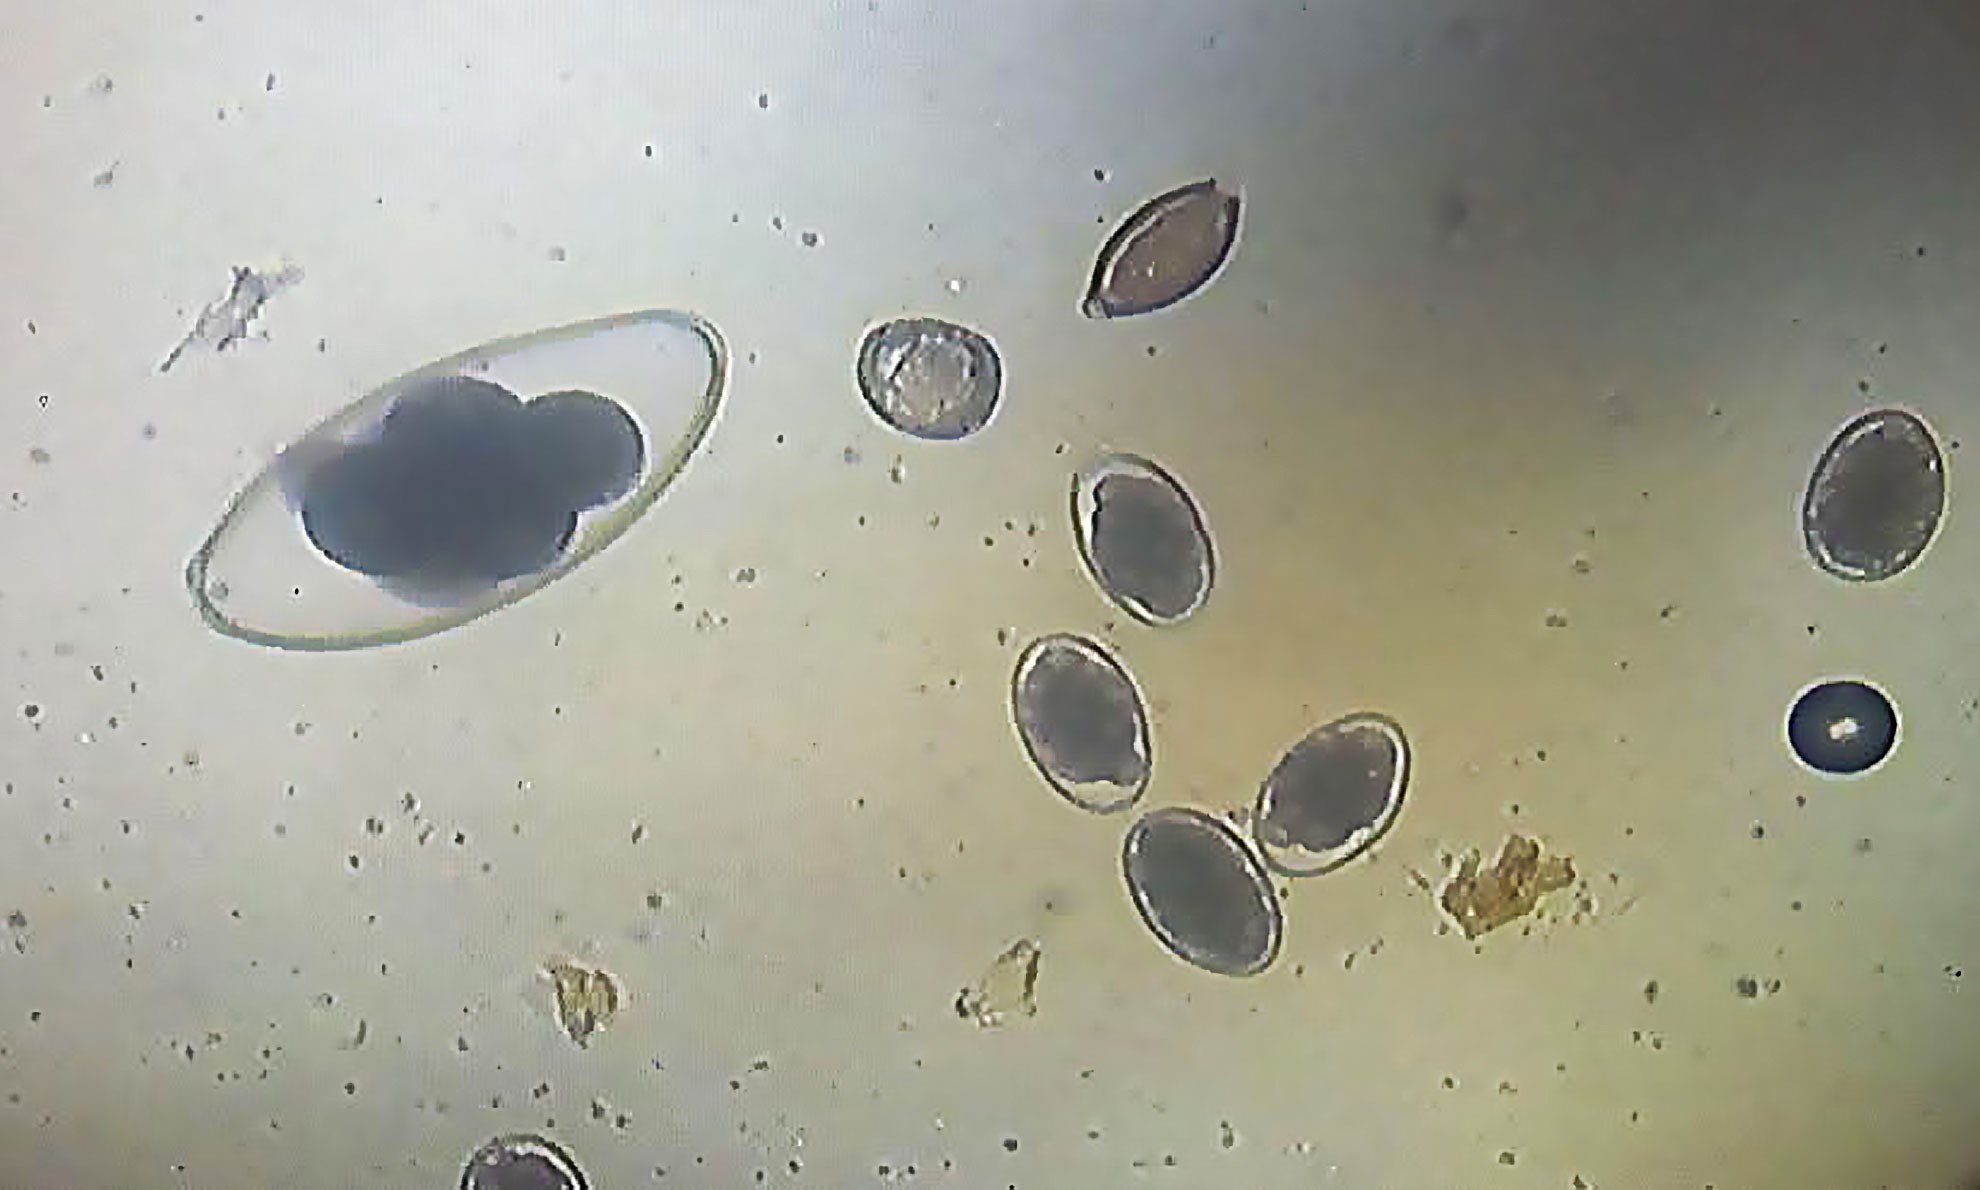

Anthelmintics or antihelminthics are a group of antiparasitic drugs that expel parasitic worms (helminths) and other internal parasites from the body by either stunning or killing them and without causing significant damage to the host. They may also be called vermifuges (those that stun) or vermicides (those that kill). Anthelmintics are used to treat people who are infected by helminths, a condition called helminthiasis. These drugs are also used to treat infected animals.